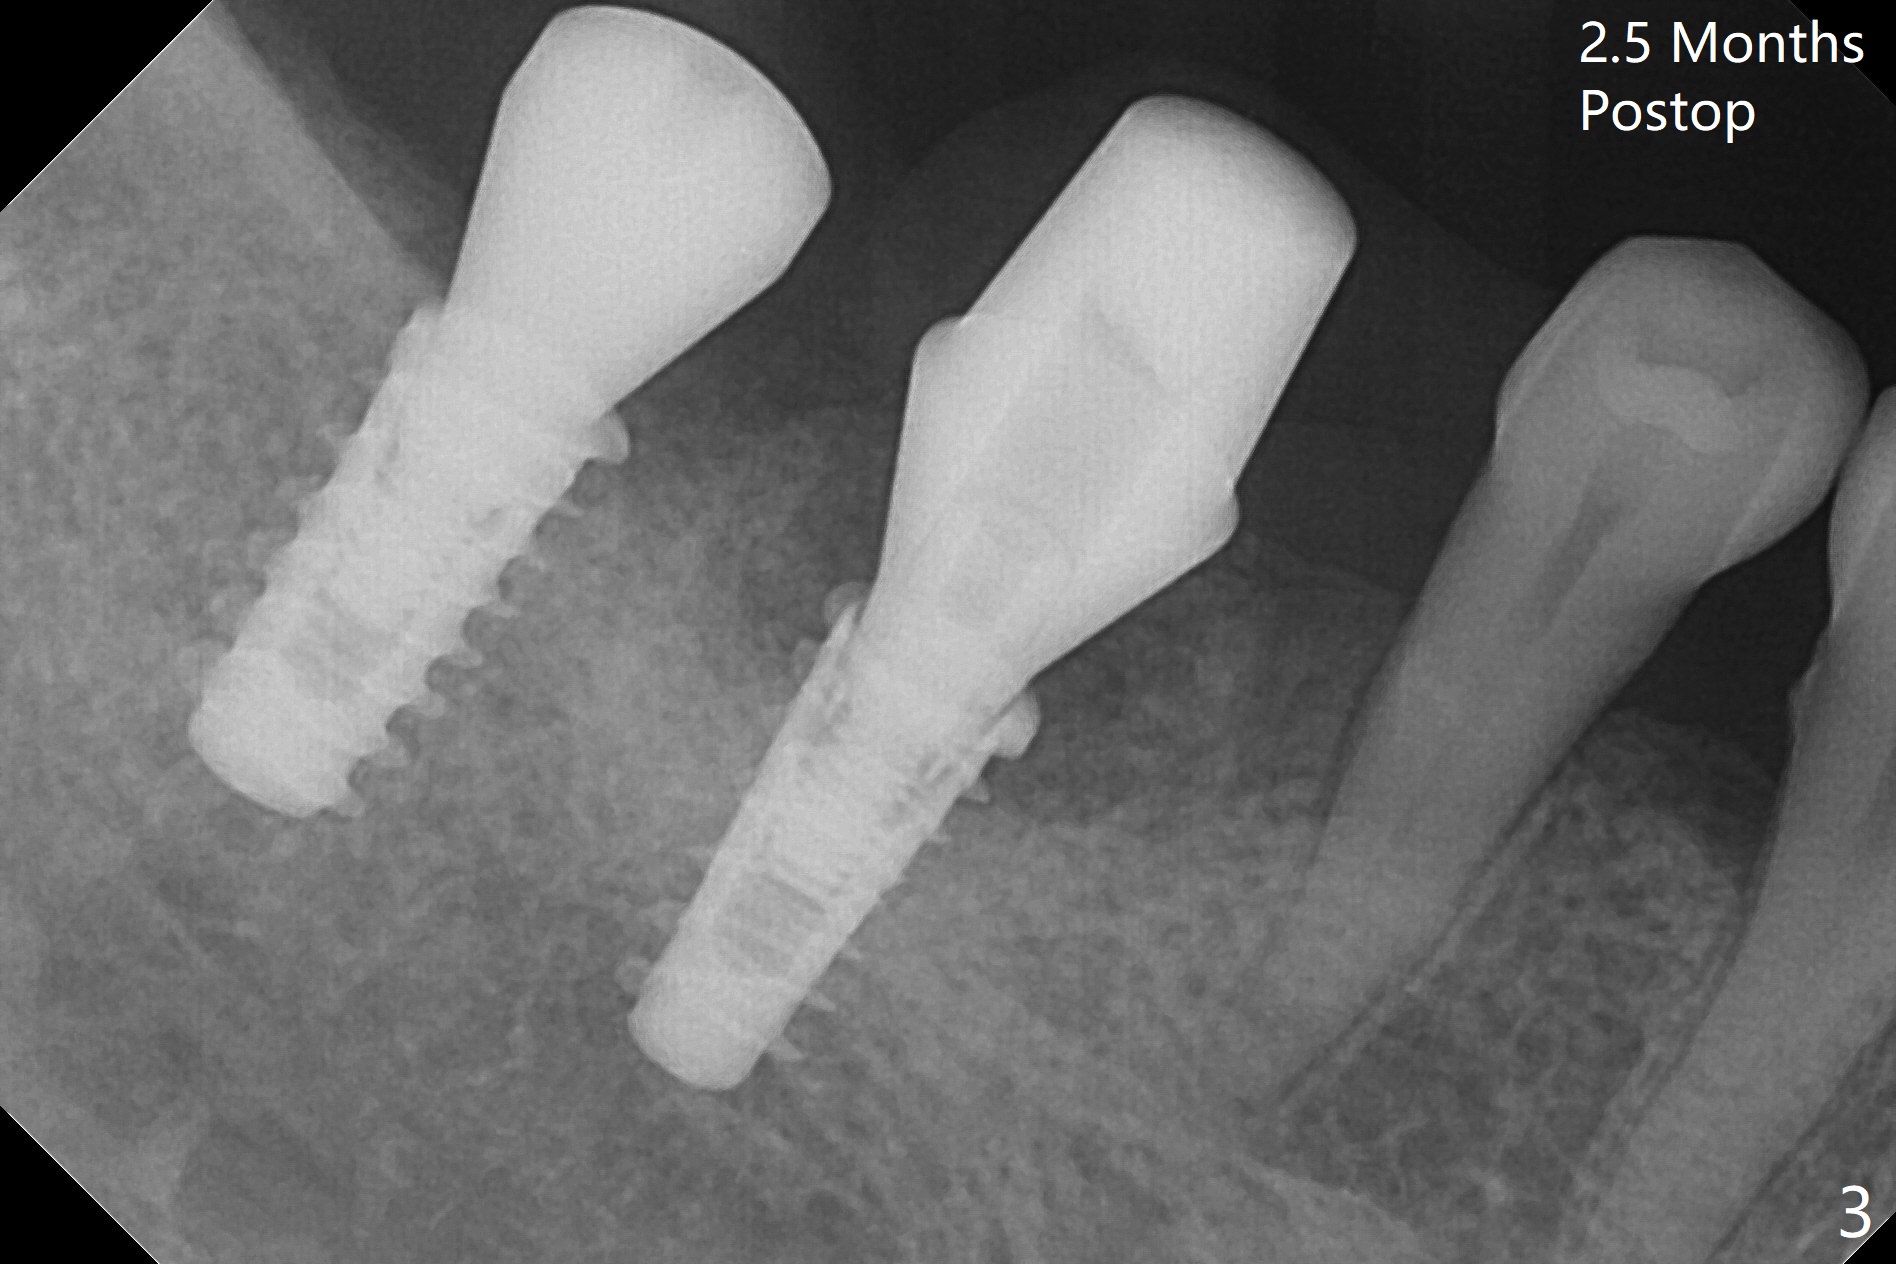

Following osteotomy, 4.5x11 and 5x9 mm dummy implants are placed at the sites of #30 and 31, respectively (Fig.1).  Due to limited inventory of Magicore and patient's in-cooperation, FC implants (4.5x9 and 5x9 mm) are placed (Fig.2).  A healing abutment (6x4 mm) is placed at #31 because of low torque (overprep), while a pair abutment (6.5x5.7(4) mm) is placed at #30.  Vera Graft is placed with autogenous bone (*).  The implant/abutment ratio at #30 is unfavorable.  If the implant turns out to be loose, immediate implant should be larger in the future.  Note bone growth, especially at #30, 2.5 and 4 months postop (Fig.3,4).  In fact the abutments are incompletely seated.  The crown of #30 is loose 2 years 8 months post cementation, while the abutment at #31 remains incompletely seated (Fig.5).  The latter is completely reseated after separating the crown, while a smaller one is seated at #30 (Fig.6) due to use of a small healing abutment earlier (Fig.5).  A good piece of news is the presence of the bone between the implants (Fig.5,6 *), which contributes to interimplant papilla.  Return to Lower Molar Immediate Implant, Prevent Molar Periimplantitis (Protocols, Table), IBS77, 2-5 Xin Wei, DDS, PhD, MS 1st edition 09/22/2017, last revision 12/01/2020